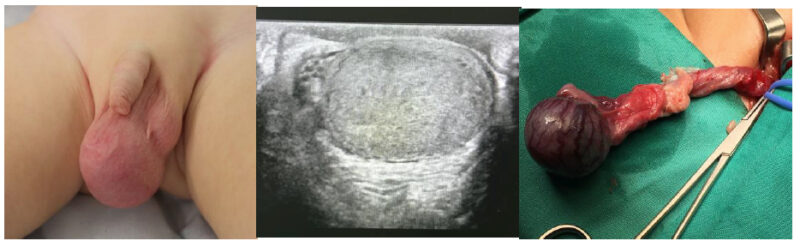

Testículo no descendido

El testículo no descendido corresponde a una de las malformaciones genitales más frecuente en niños. Su incidencia en recién nacidos de término es de 1,5 – 4% y en prematuros puede llegar a 45%(1,2). Durante los primeros meses post parto puede existir un descenso testicular espontáneo. Este descenso generalmente ocurre en los primeros tres meses y es secundario al estímulo hormonal natural que existe en este período, conocido como “mini pubertad”. Por esta razón, en pacientes de término y tras cumplir 6 a 12 meses de vida, la incidencia baja al 1%. La clasificación más utilizada actualmente es aquella que divide los testes no descendidos en palpables (80%) y no palpables (20%)2. La figura 1 resume las principales formas de presentación del testículo no descendido.

– Testículo intraabdominal viable (40%).

– Testículo ausente y vasos sanguíneos ciegos a nivel del anillo inguinal profundo (20%).

– Testículo atrófico (evanescente) inguinal: vasos sanguíneos y deferente ingresando por canal inguinal con conducto inguinal profundo generalmente cerrado (30%).

– Testículo normal en el canal inguinal, vasos sanguíneos y deferente ingresando por canal inguinal con conducto inguinal profundo generalmente abierto (10%).

La técnica quirúrgica va a depender del hallazgo intraoperatorio y de las características del testículo. En aquellos testículos de buen aspecto se puede realizar el descenso testicular y orquidopexia en un tiempo. Esto consiste en liberar los vasos espermáticos y los elementos del gubernáculum permitiendo la llegada del testículo al canal inguinal. Esta técnica es más utilizada en los testículos no palpables tipo “peeping”, donde el teste esta a nivel del anillo inguinal profundo, entrando y saliendo de este. También se puede hacer descenso y orquidopexia en dos tiempos (Fowler-Stephens), donde en el primer tiempo se seccionan los vasos espermáticos, esperando que, en un periodo mínimo de 6 meses, la vascularización vía arteria deferencial del teste permita su descenso sin problemas. El riesgo de atrofia testicular con esta técnica es de aproximadamente un 10-15%1. La figura 2 resume las opciones terapéuticas en el manejo del testículo no descendido.